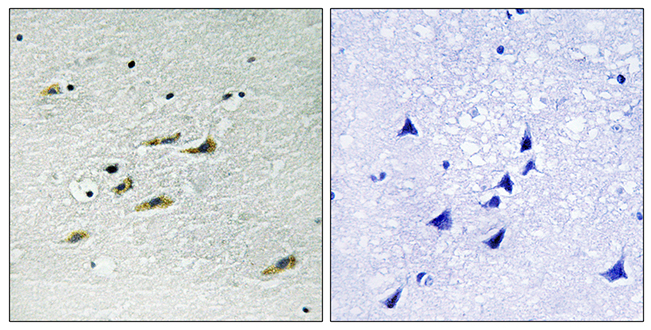

Anti-GRM1 AntibodyA97783

ApplicationsELISA, ImmunoHistoChemistry

ReactivityHuman, Mouse, Rat